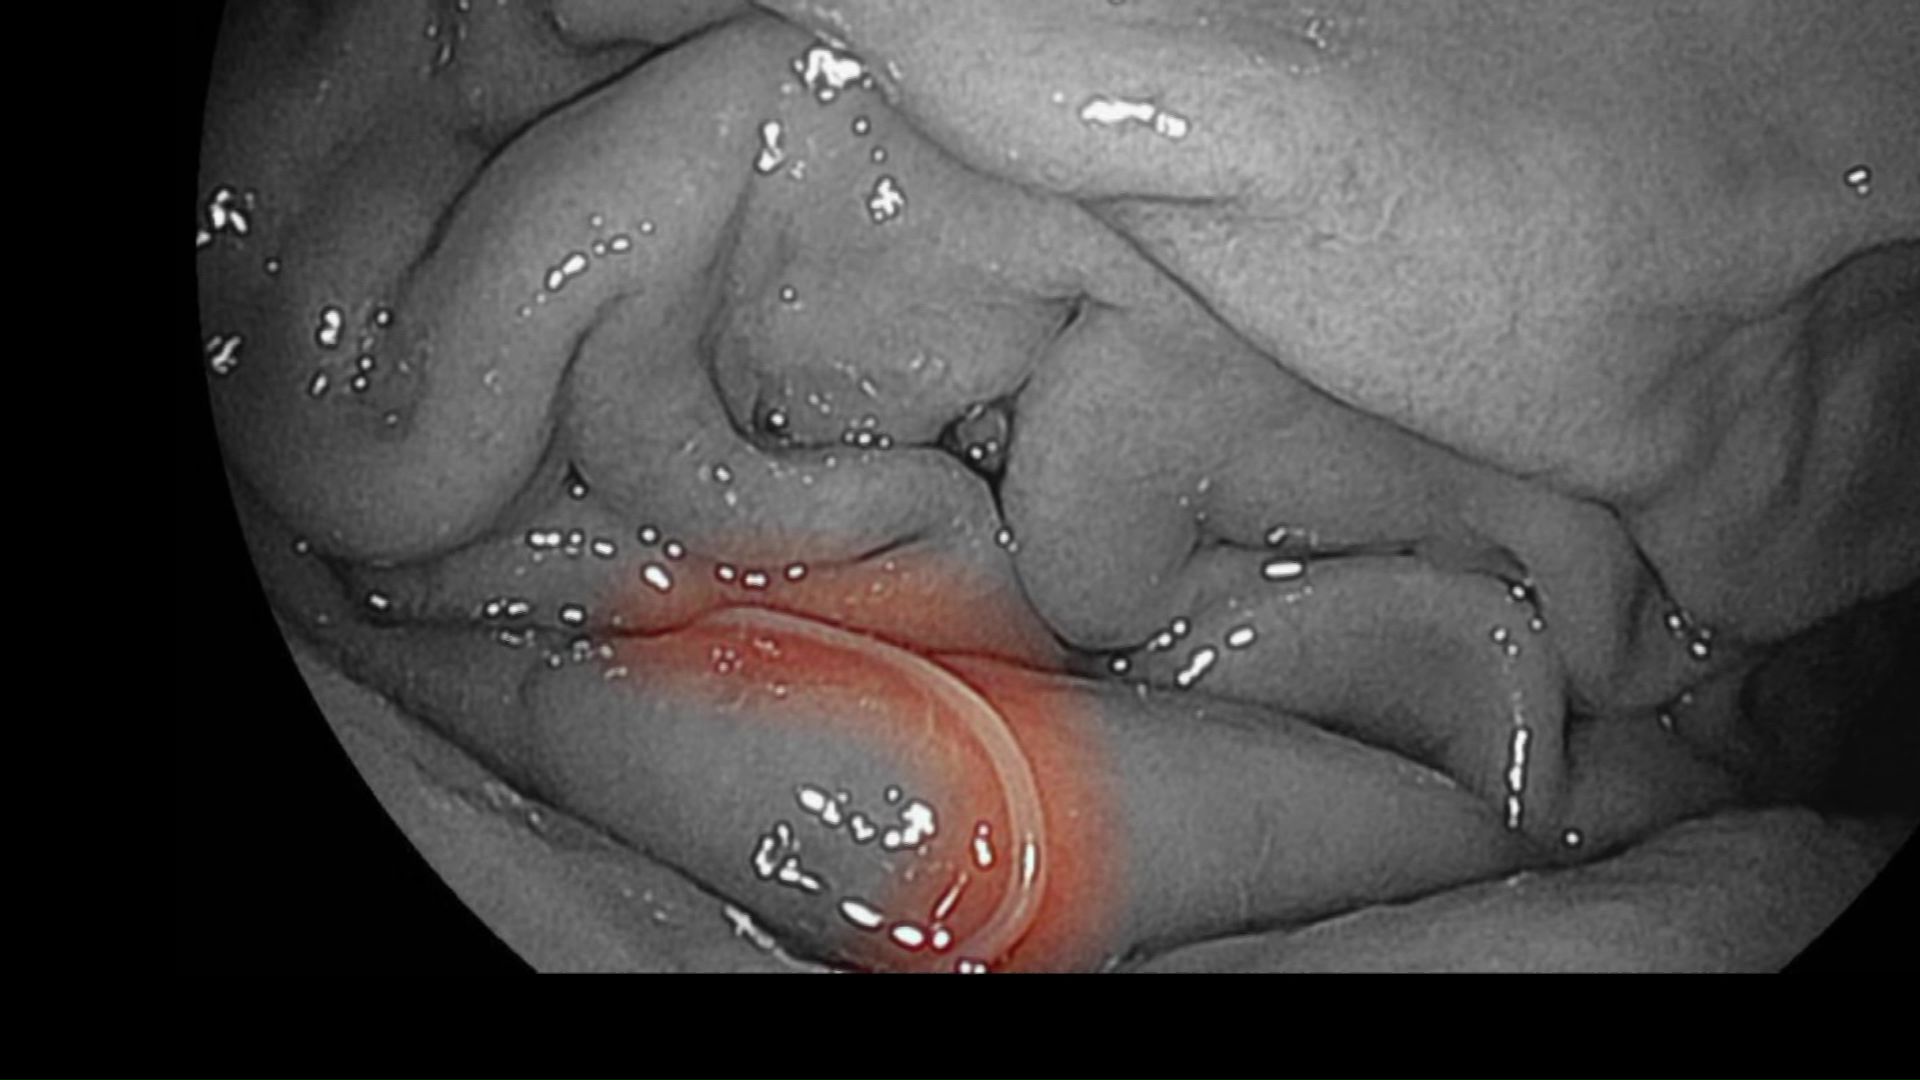

どうにか病院に行って胃カメラで検査すると、モニターに映ったのは白い糸くずのようなアニサキスでした。